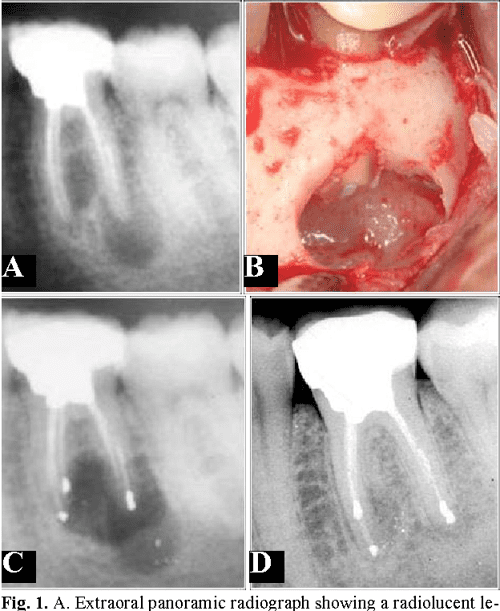

(PDF) New perspectives in periapical surgery Ostectomy and osteotomy

(PDF) New perspectives in periapical surgery Ostectomy and osteotomy Ostectomy Vs Osteoplasty Osseous resective surgery is a periodontal treatment that modifies the bony support of the teeth to eliminate pockets and correct. Learn why it's necessary, how it's done, and what to expect after the surgery. Osteoplasty is defined as reshaping alveolar bone to achieve a more physiological form without removal of supporting bone. Osseous surgery reduces the pockets around your teeth. Ostectomy Vs Osteoplasty.